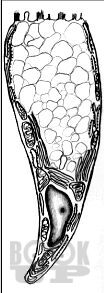

В предлагаемом учебном пособии, состоящем из 7 разделов, представлены сведения о последовательности развития и гистологическом строении органов ротовой полости человека. Для каждого раздела обозначена цель, вопросы для самостоятельной подготовки, представлен информационный блок, описание микропрепаратов. С целью самоконтроля приводится перечень тестовых заданий, ситуационных задач и ответы на них.